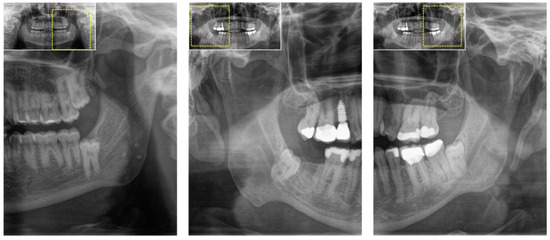

- Al-Haj Husain, A.; Schmidt, V.; Valdec, S.; Stadlinger, B.; Winklhofer, S.; Schönegg, D.; Sommer, S.; Özcan, M.; Al-Haj Husain, N.; Piccirelli, M. MR-orthopantomography in operative dentistry and oral and maxillofacial surgery: A proof of concept study. Sci. Rep. 2023, 13, 6228. [Google Scholar] [CrossRef] [PubMed]